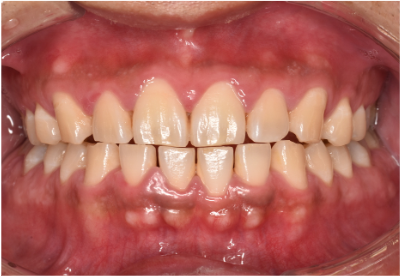

一般歯科 2023.0330代男性「検診をしてほしい」歯茎の炎症と付着していた歯石を、ブラッシング指導と歯石除去による歯周病治療で改善した症例